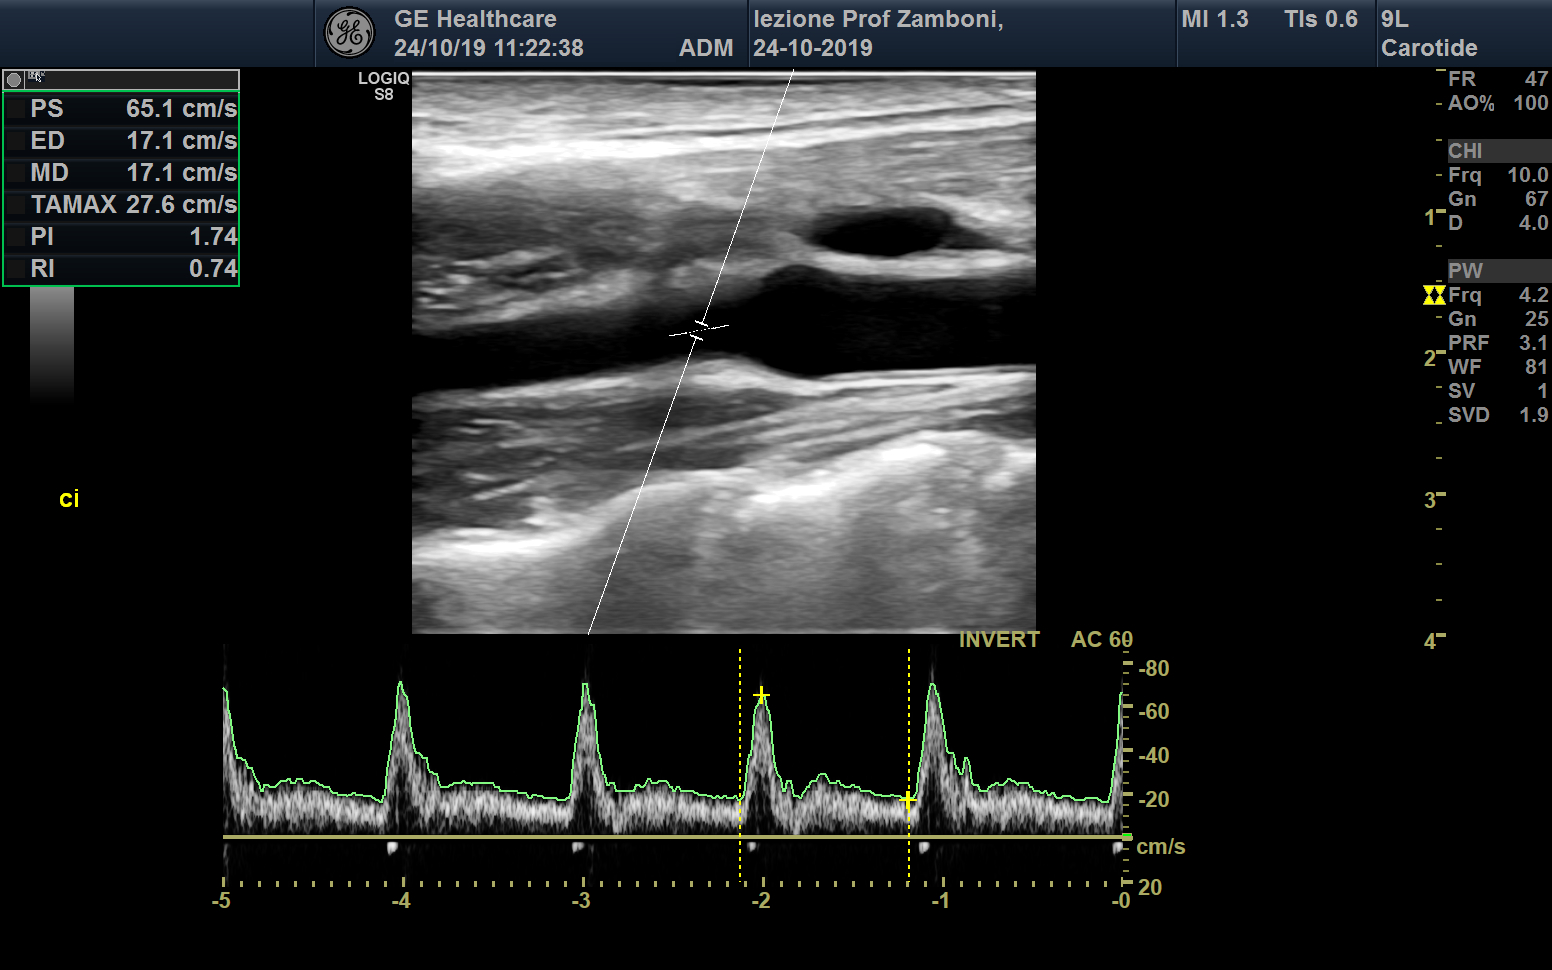

PW Carotide interna

JPEG image icon PW Carotide interna.jpg — JPEG image, 571 kB (585227 bytes)